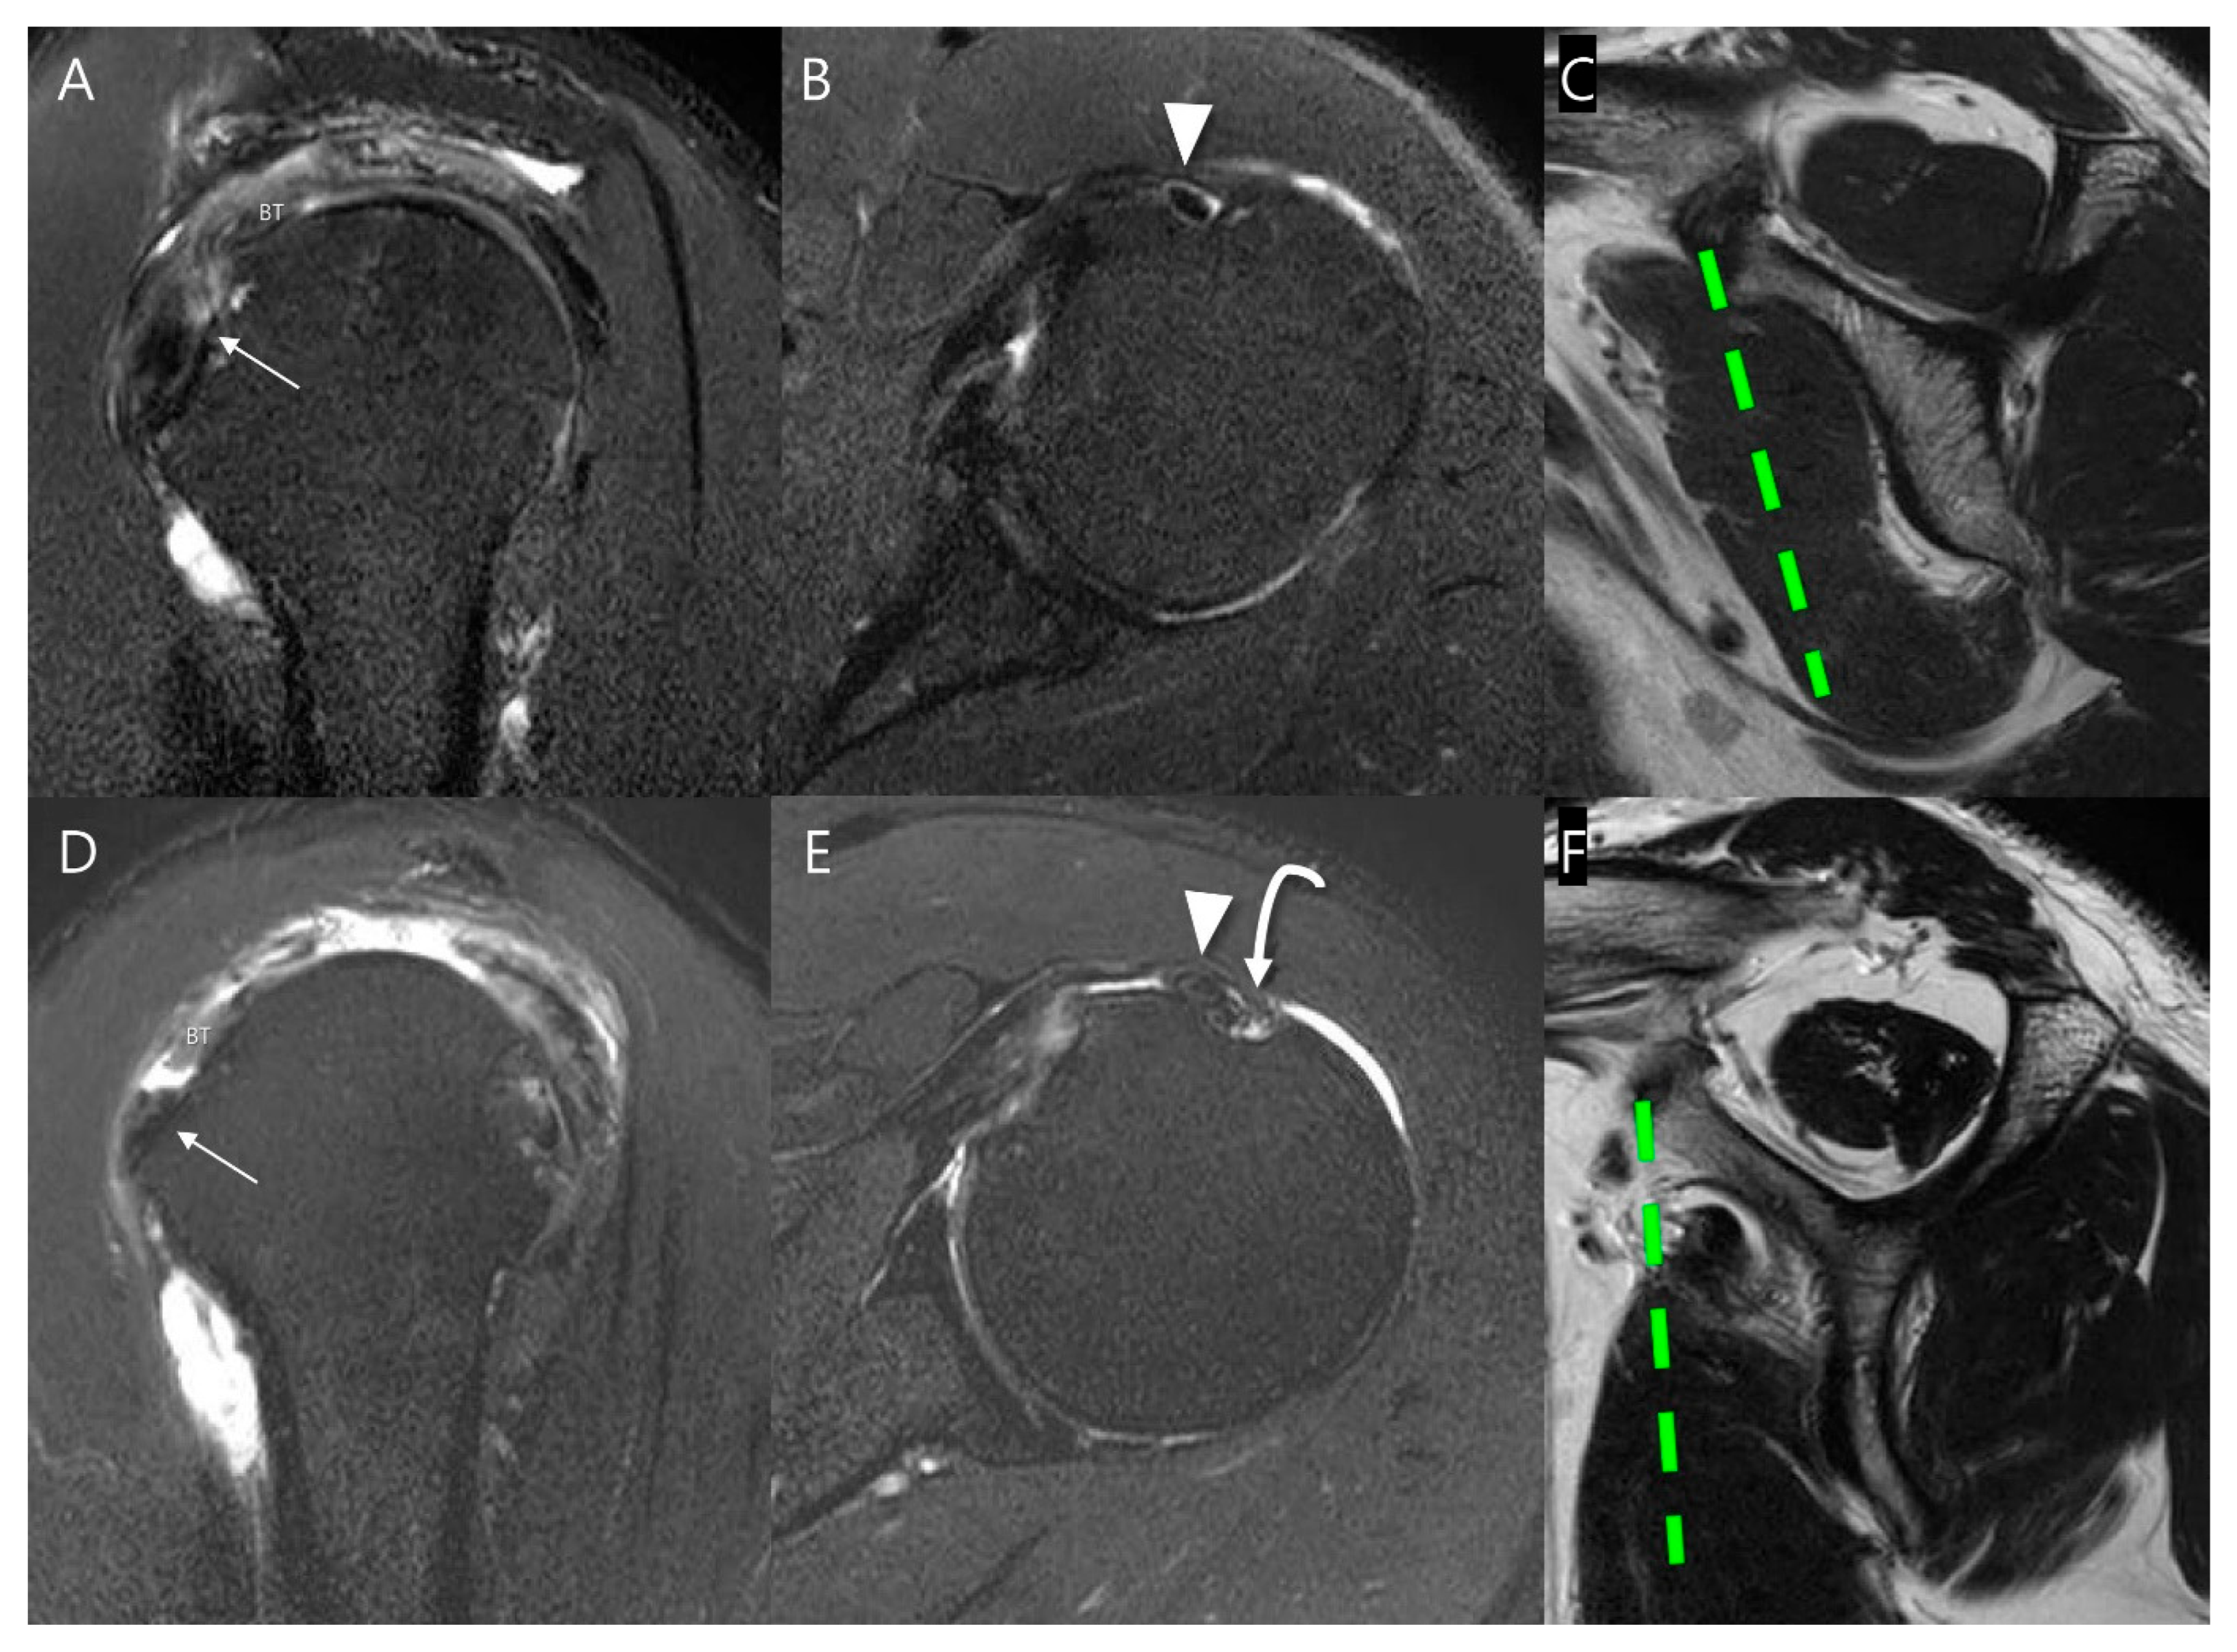

| Subscapularis muscle atrophy | <0.001 | κ = 1.000 (p < 0.001) | ||

| None to mild degrees (%) | 110 (99.1) | 21 (65.6) | ||

| Moderate to severe degrees (%) | 1 (0.9) | 11 (34.4) | ||

| Subscapularis muscle fatty infiltration | <0.001 | κ = 0.818 (p < 0.001) | ||

| None to some fatty streaks (grade 0 and 1, %) | 109 (98.2) | 25 (78.1) | ||

| Less or more than 50% of fat than muscle (grade 2 and 3, %) | 2 (1.8) | 7 (21.9) | ||

| Subluxation or dislocation (%) | 13 (12.1%) | 22 (81.5%) | <0.001 | κ = 0.853 (p < 0.001) |